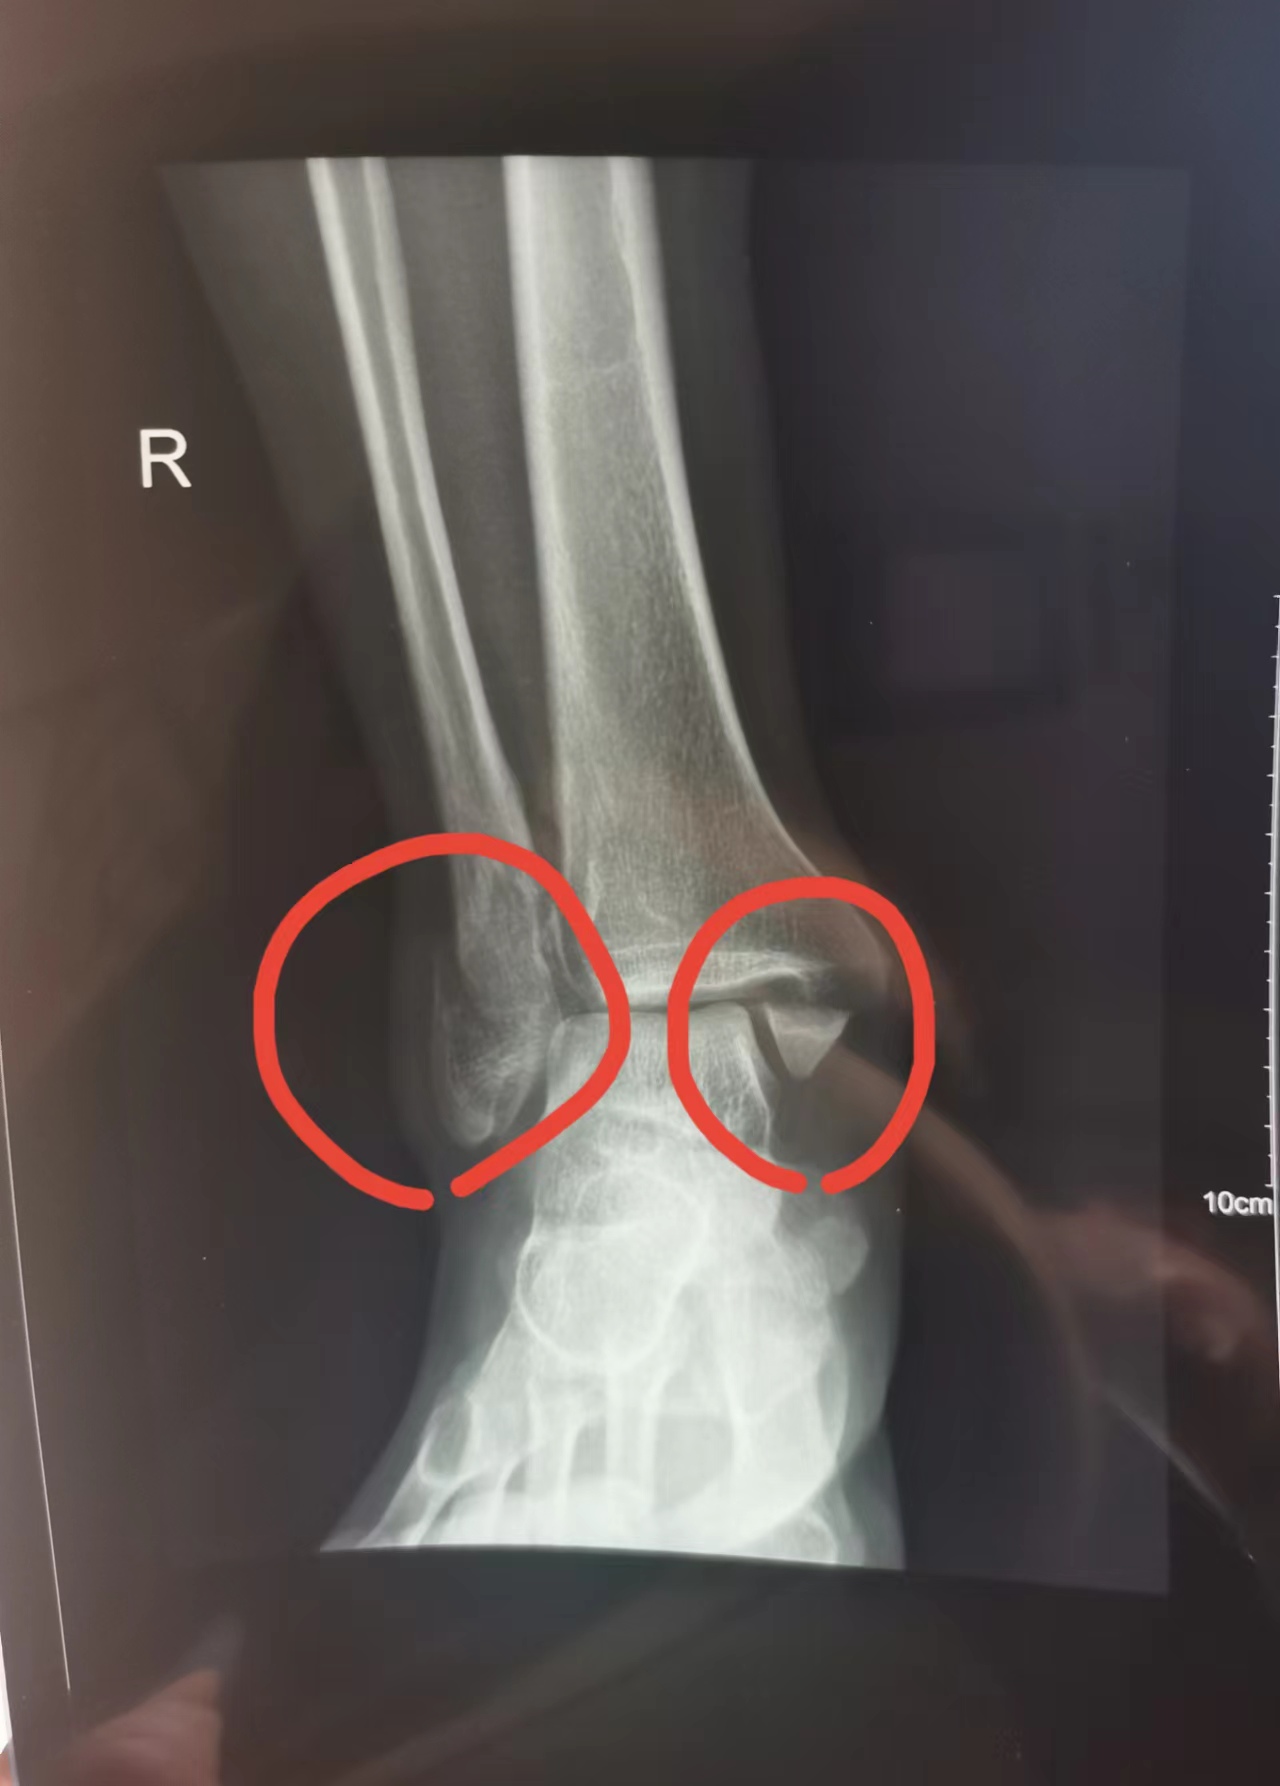

这一张,看起来好象比较清晰了

2月27日,术前DX、CT。躺着床上,护工推着去检查,眼望天花板,那感觉挺怪。再次确诊:右侧内外后踝及胫骨腓切迹骨折,骨折线清晰,断端分离,周围软组织稍肿胀,右侧内踝间隙增宽。